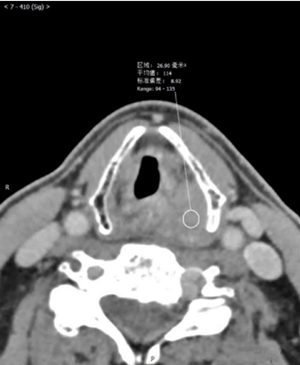

影像图片

评论: 声门上层面喉左后壁增厚,呈软组织密度肿块影,边界不清,左侧杓状软骨大部分显示不清,左侧甲状软骨边缘毛糙,增强扫描呈渐进性轻度强化。